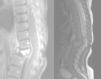

A las 24h del alta reaparece la fiebre. En la exploración física destaca protrusión en la región dorsal baja con angulación vertebral. Se realiza radiografía dorsolumbar que muestra cifoescoliosis con desaparición casi total del cuerpo vertebral de L1 compatible con espondilitis (fig. 1). Se recoge hemocultivo y se inicia cobertura antibiótica con cloxacilina y cefotaxima. Se realiza nueva RM de columna que muestra aplastamiento vertebral de L1 y cambios circundantes que sugieren espondilodiscitis con colección flemonosa de D11 a L1–L2 (fig. 2). No presenta, sin embargo, ningún hallazgo patológico en la nueva gammagrafía ósea realizada (99mTc-HMDP). Se optimiza la antibioterapia a teicoplanina y cefotaxima, que se prolonga durante dos semanas y se coloca un corsé ortopédico. Posteriormente completa 6 semanas más de tratamiento antibiótico oral con cefadroxilo a 100mg/kg/d.